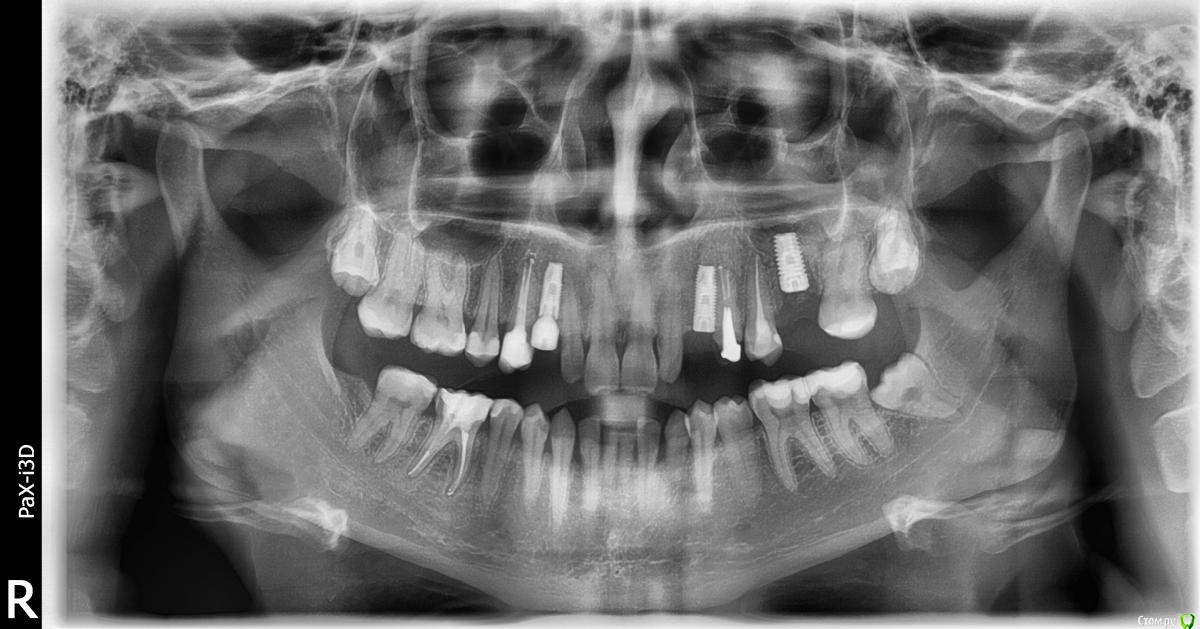

fifa888.dexo Опубликовано 4 марта, 2016 Поделиться Опубликовано 4 марта, 2016 (изменено) Здравствуйте!Ровно 9 месяцев назад установили 3 импланта в верхнюю челюсть.Были некоторые проблемы и осложнения.Я создавала тему вот здесь http://forum.stom.ru/topic/29800-uvazhaemye-vrachi-khirurgi-implantologi-pomogite/.На данный момент вроде бы все разрешилось..3 недели назад установили формирователи на оставшиеся 2 импланта,на 1 стоял сразу. Подошло время протезирования.Я сделала снимок чтобы посмотреть в норме ли перелеченные каналы и увидела кое что еще...Сразу оговорюсь с 26 было воспаление в пазухе итд. Но с 23 было все в норме,он был зашит и никак не беспокоил.1. Я ошибаюсь или кость ушла???2. Почему такое могло произойти?3. Что делать?Прикрепляю два снимка один панорамный сделан через месяц после имплантации, второй прицельный сегодня. Есть кт но срезы делать я совершенно не умею. Изменено 4 марта, 2016 пользователем fifa888.dexo Ссылка на комментарий

red_butler Опубликовано 6 марта, 2016 Поделиться Опубликовано 6 марта, 2016 Справа формирователь десны не докручен. Ссылка на комментарий

red_butler Опубликовано 14 марта, 2016 Поделиться Опубликовано 14 марта, 2016 по снимку все нормально и с имплантом и с синусом.P.S. похоже проведен закрытый синуслифтингhttp://i053.radikal.ru/1603/4b/6b8f464e7e3e.jpghttp://s017.radikal.ru/i426/1603/ad/6495c35c8e8e.jpg Ссылка на комментарий

TIGER Опубликовано 15 марта, 2016 Поделиться Опубликовано 15 марта, 2016 Спасибо Вам большое!А то я все переживаю и перживаю)))Был проведен открытый синус лифтинг,но на 5 день в пазухе было воспаление и гной, био осс осыпался немного как я поняла.Решили спасать.И с тех пор время от времени пазуха вообще не дышит, иногда пристуствует чувство давления. Раньше никогда никаких гайморитов и пр. не было. Отсюда мои волнения). Не хочу показаться настырной, но не могли бы еще сказать как дело обстоит с клыками?По кт можно увидеть нет ли там резорбции?Особенно беспокоюсь за 23,так как там очень близко к зубС пазухой всё отлично)Не переживайте)Синус проведён удачно судя по снимку 1 Ссылка на комментарий